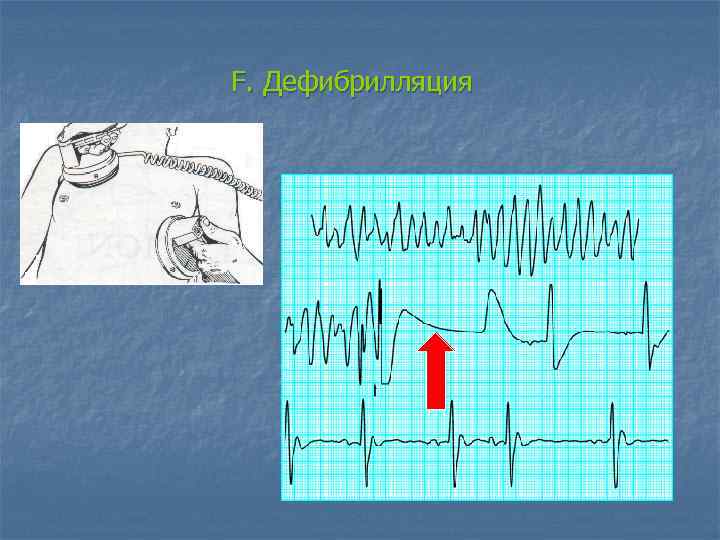

F. Дефибрилляция

Дефибрилляция w w Энергия разрядов (200 Дж – 300 Дж - 360 Дж) Серия из 3 разрядов должна быть проведена менее чем за 1 минуту w Не следует останавливаться между разрядами на СЛР w После проведения разряда оценивайте каротидный пульс NB! Если сразу после разряда на ЭКГ регистрируется асистолия, не следует вводить адреналин/атропин! Необходимо проведение СЛР в течение 1 минуты и затем оценка ритма и проверка пульса